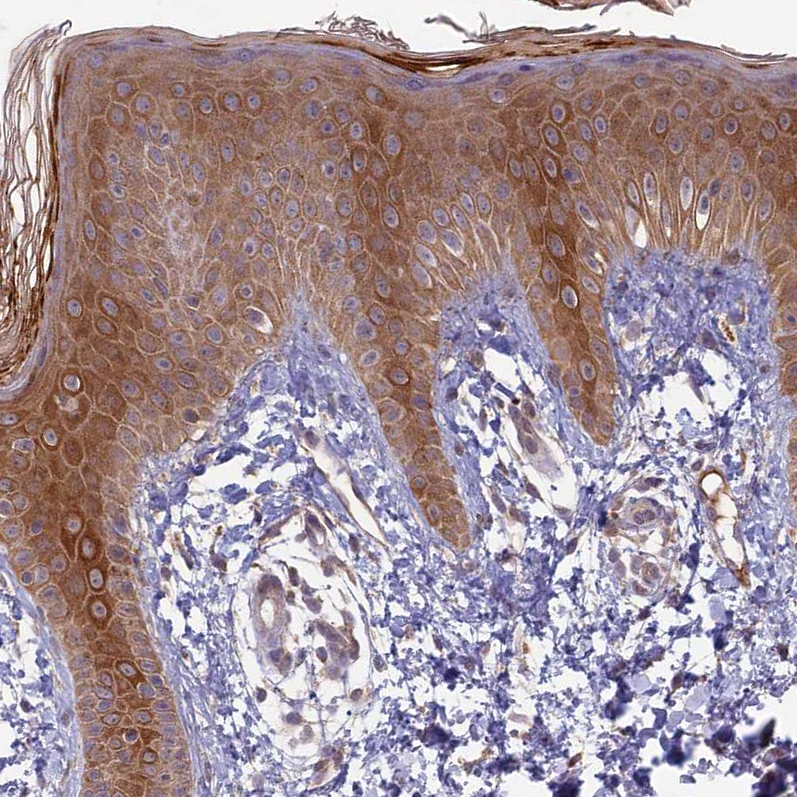

Immunohistochemical staining of human fallopian tube, skin, small intestine and testis using Anti-RCCD1 antibody HPA039683 (A) shows similar protein distribution across tissues to independent antibody HPA040776 (B).